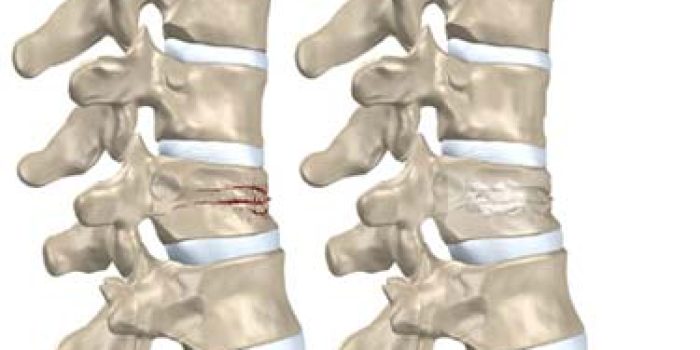

| شکستگی ستون فقرات همیشه به عنوان یک صدمه وخیم شناخته میشود و برخورد با آن کاملا باید با دقت انجام شود، زیرا ممکن است آسیب به نخاع را همراه داشته باشد. بعد از سقوط ، احساس هر گونه درد در پشت به هنگام نشستن و نیز ملاحظه هر گونه جراحت آشکار در این نواحی را باید به منزله شکستگی مهرهها تلقی نمود مگر آن که خلاف آن ثابت شود. افتادن جسم سنگین روی پشت و یا سقوط از بلندی به طوری که ستون فقرات با جسمی برخورد کند یا روی باسن یا جفت پاها افتاده باشد و یا سقوط بر روی سر ، مثل شیرجه رفتن در استخر ، میتواند باعث شکستگی ستون فقرات شوند |

عارضه خطرناک شکستگی ستون فقرات عبارت است از آسیب رسیدن به نخاع و اعصاب نخاعی که به علت فشار قطعات شکسته استخوان یا به علت دررفتگی مهرهها و یا خونریزی ایجاد میشود. آسیب نخاعی و اعصاب آن سبب اختلالات حسی و حرکتی و فلج در قسمت زیر ناحیه آسیب دیده میشود.

در صورت قطع نخاع بوسیله قطعه شکسته مهره ، نخاع هیچوقت ترمیم نخواهد شد و مصدوم تا آخر عمر از سطح شکستگی به پایین فلج خواهد شد. بنابراین روش برخورد اولیه با مصدوم خیلی حیاتی است.